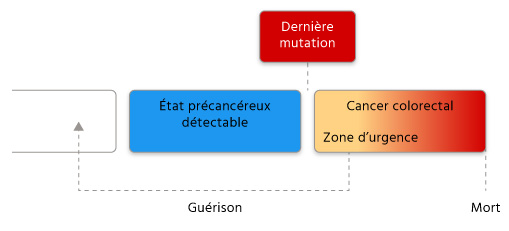

Que se passe-t-il ensuite pour eux ? Tout va dépendre de leur réactivité. Si ces personnes mettent trop de temps à déceler les cellules cancéreuses qui se multiplient à leur insu dans le côlon, elles continuent de dériver vers la droite de la flèche, se rapprochant cette fois d’un point de non-retour : la mort. Chaque année, 18 000 personnes empruntent cette voie funeste à sens unique.

En revanche, si la tumeur est détectée alors qu’elles se trouvent encore suffisamment proche du point d’apparition (dans la « zone d’urgence »), elles peuvent encore espérer échapper au pire. La prise en charge médicale permet en quelque sorte d’arrêter la progression, et en cas de guérison, elles retournent vers l’arrière, à une certaine distance du cancer colorectal.